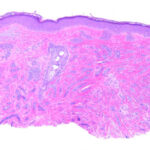

Histopathologic examination reveals a relatively well-circumscribed lesion in the upper two-thirds of the dermis with a focal epidermal connection. It is composed of basaloid aggregations arranged predominantly in columns and cords and admixed with infundibulocystic structures, surrounded by a dense, hypocellular desmoplastic stroma. It may occasionally be difficult to distinguish this entity histologically from malignant desmoplastic lesions such as aggressive growth basal cell carcinoma or MAC. Treatment. Local surgical excision is the preferred treatment